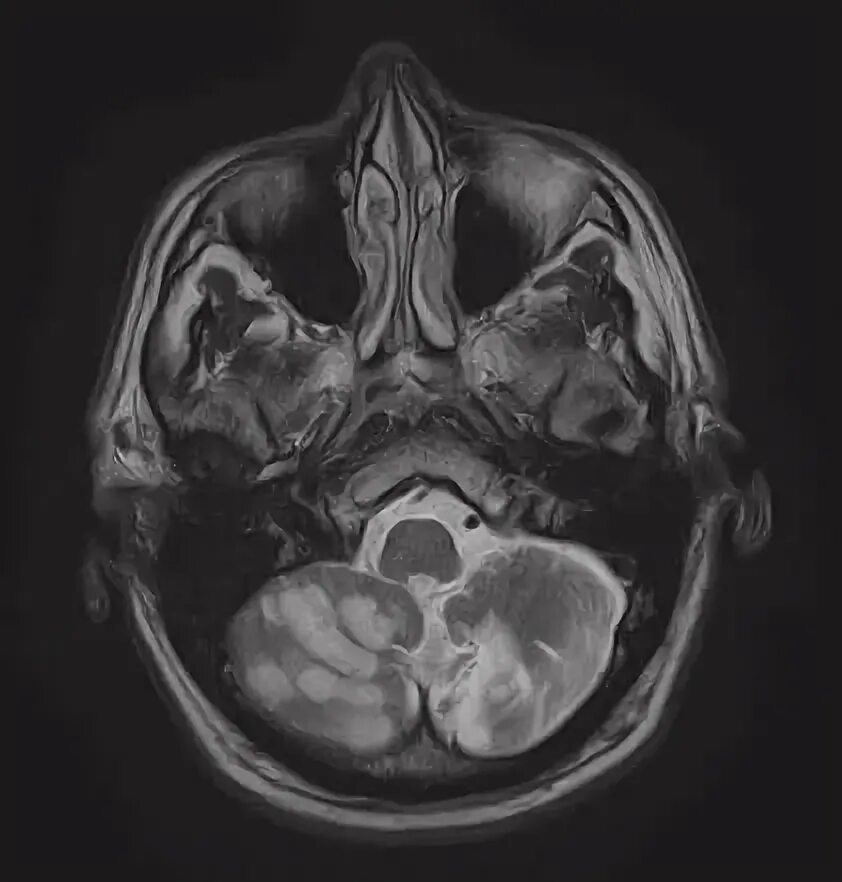

Мрт височных костей в режиме dwi